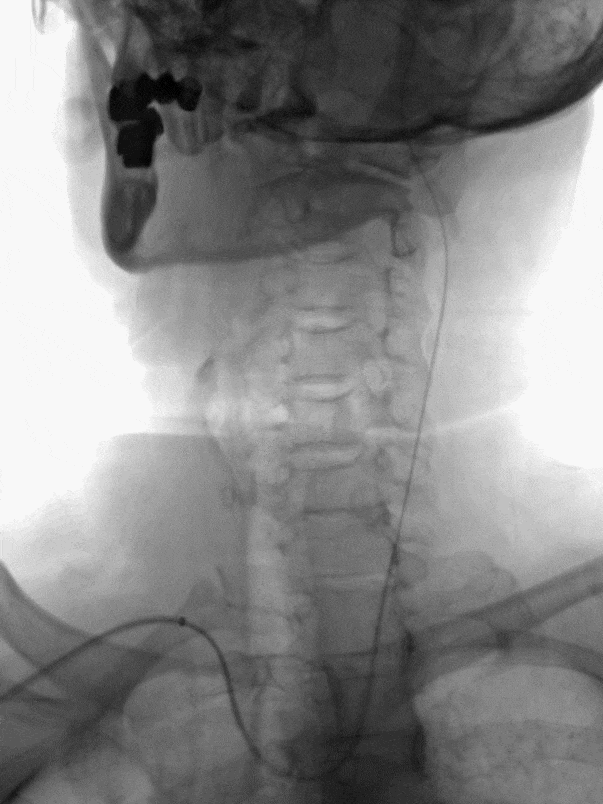

泥鳅导丝、SIM2造影导管、5.5F Introsky X导管鞘同轴下继续跟进,尽可能高到位,随后引入V-18导丝。

Catalyst 6 中间导管在5.5F Introsky X导管鞘内输送顺利,微导丝、微导管超选越过闭塞段。